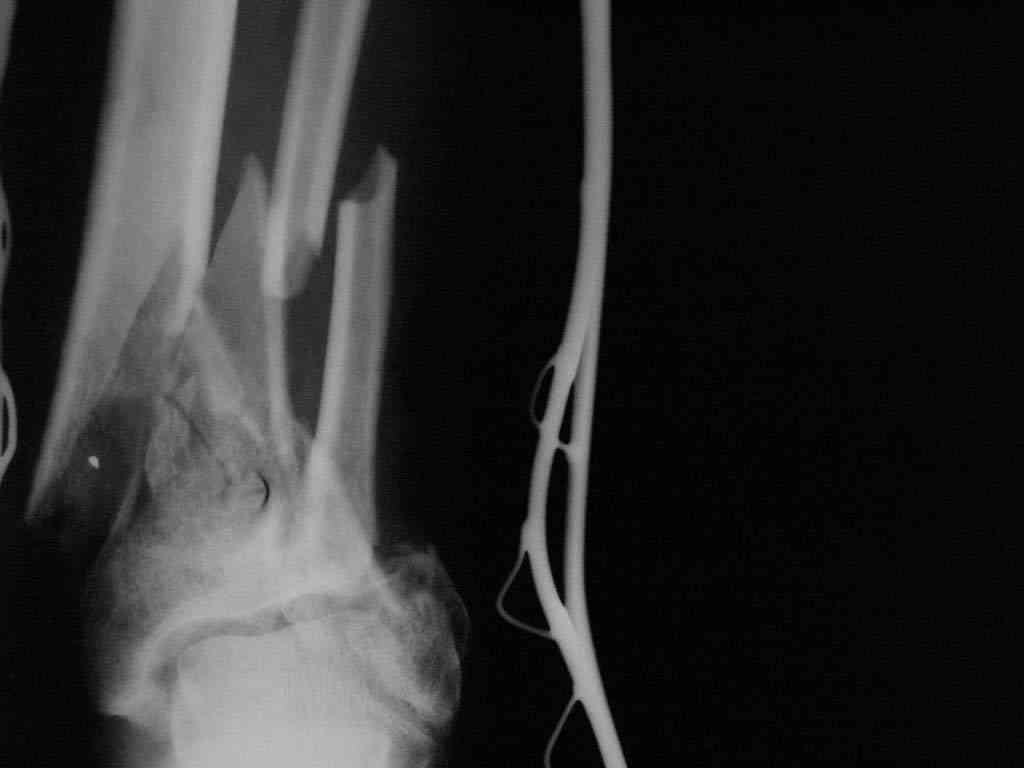

В последующем перевязки раны с "Левомеколь", через 3 недели с момента травмы в ране определялись грануляции, нежизнеспособный конец дистального отломка. 10.11.08 ВХО раны, резекция дистального отломка на 3 см, перемонтаж

аппарата наружной фиксации (см. Р-граммы). Отломки сближены на 2 см (остеотомию малоберцовой не делали). В настоящее время (5 сутки после операции) незначительное количество серозного отделяемого из раны, имеется дефект кости 4 см

(см. Р-граммы).

Представляем рентгенограммы левой голени при поступлении, после повторного оперативного лечения и фото st.localis на 14.11.08.